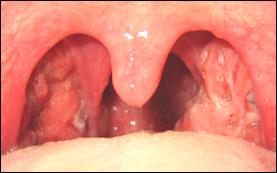

Las amígdalas ó anginas son un par de masas con aspecto de almendra formadas también por tejido linfoide. Cada una está situada a cada lado de la garganta. Muestran unas pequeñas depresiones llamadas criptas. Pueden verse relativamente fácil al abrir la boca, iluminando la garganta con una lamparita. Se cree que intervienen en la defensa contra las enfermedades; sin embargo, su infección crónica por virus y bacterias pueden provocar distintos tipos de afecciones.